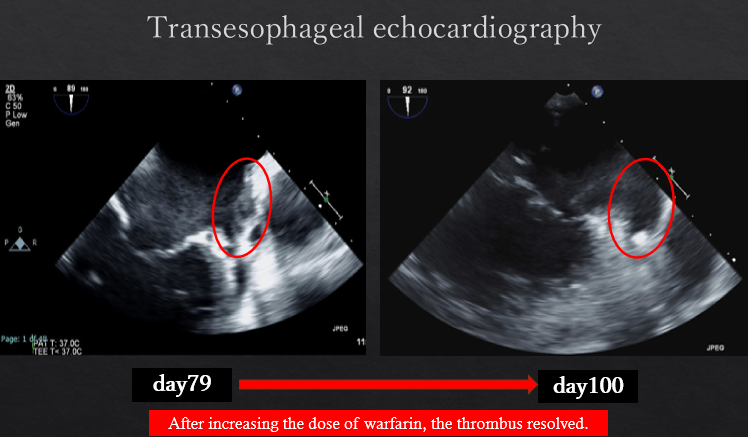

The patient had reduced left ventricular function, and tachycardia-induced cardiomyopathy was initially suspected. We therefore aimed for early restoration of sinus rhythm. Despite treatment with rivaroxaban, the patient developed a cardioembolic stroke, and a thrombus persisted in the LAA. Anticoagulation was switched to warfarin. During stroke rehabilitation and optimization of cardioprotective therapy, we monitored the thrombus for resolution, but it remained unchanged. Because an LAA occlusion device cannot be used in the presence of an existing thrombus, and thoracoscopic LAA resection is feasible when the thrombus does not extend to the LAA base, we decided to perform thoracoscopic LAA resection on hospital day 70. Intraoperative transesophageal echocardiography confirmed the absence of thrombus at the LAA base before resection. A thrombus was found within resected LAA specimen. However, postoperative computed tomography on hospital day 79 revealed hypoattenuated thickening (HAT) at the resection stump, suggestive of thrombus formation. Transesophageal echocardiography confirmed this finding. After intensifying warfarin management, the thrombus resolved approximately 20 days later. Catheter ablation was subsequently performed on hospital day 115, and the patient has since maintained sinus rhythm.